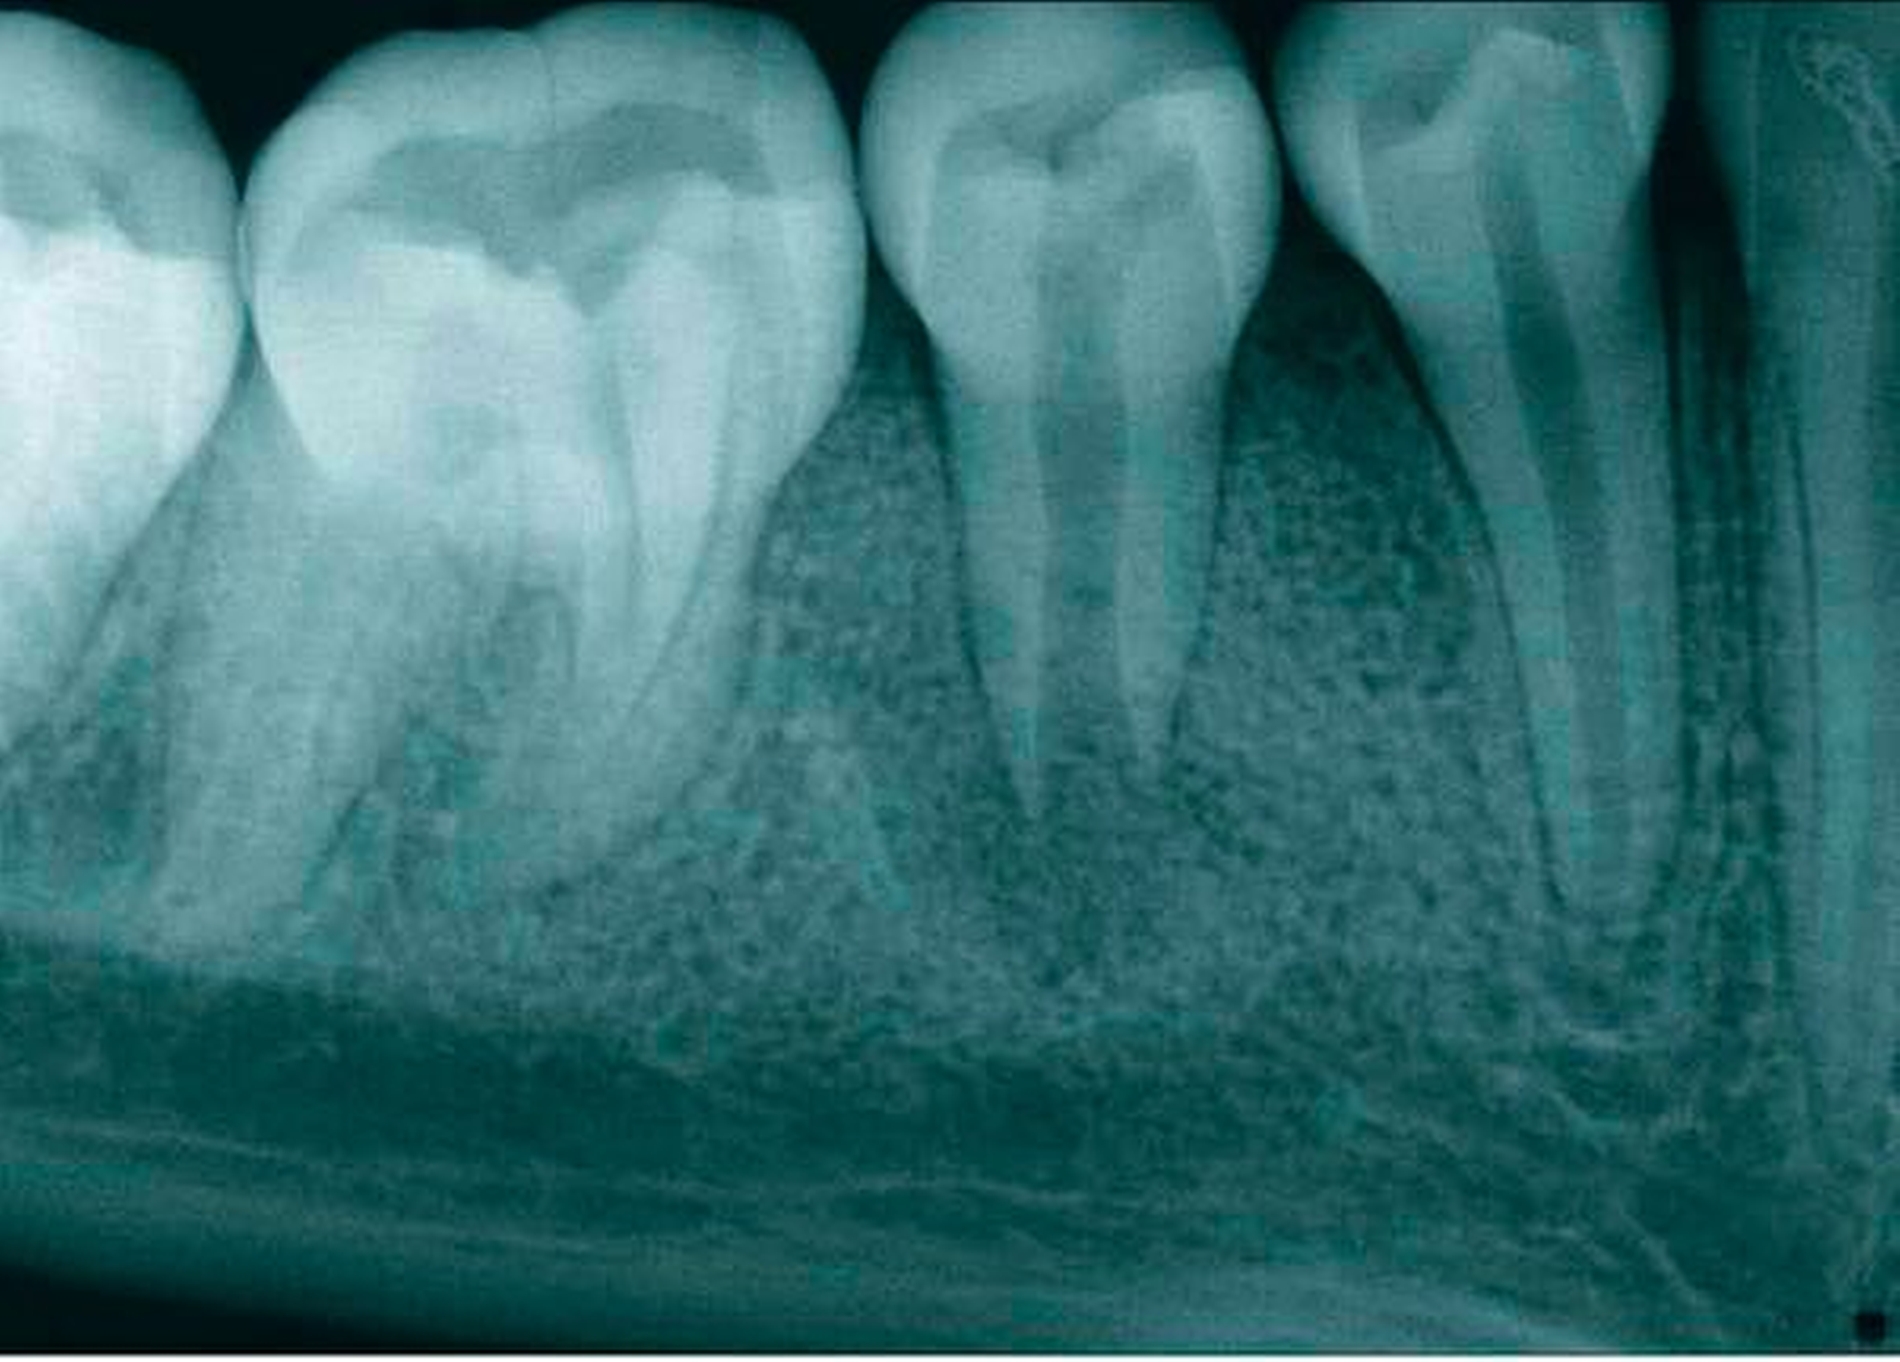

Das Ausgangsröntgenbild (Abbildung 1) der Regio 44–46 zeigte eine apikale Transluzenz im Bereich der Wurzelspitze des Zahnes 45. Der Zahn weist ein nicht abgeschlossenes Wurzelwachstum mit weit offenem Foramen und weitlumigem Wurzelkanal auf. Im Bereich der klinischen Zahnkrone imponiert eine transluzente, kariesdichte Zone, die sich vom mesialen Anteil der Krone bis ins Pulpenkavum erstreckt. Die Fissur des Zahnes scheint stark invaginiert und ist radiologisch nachzuvollziehen.